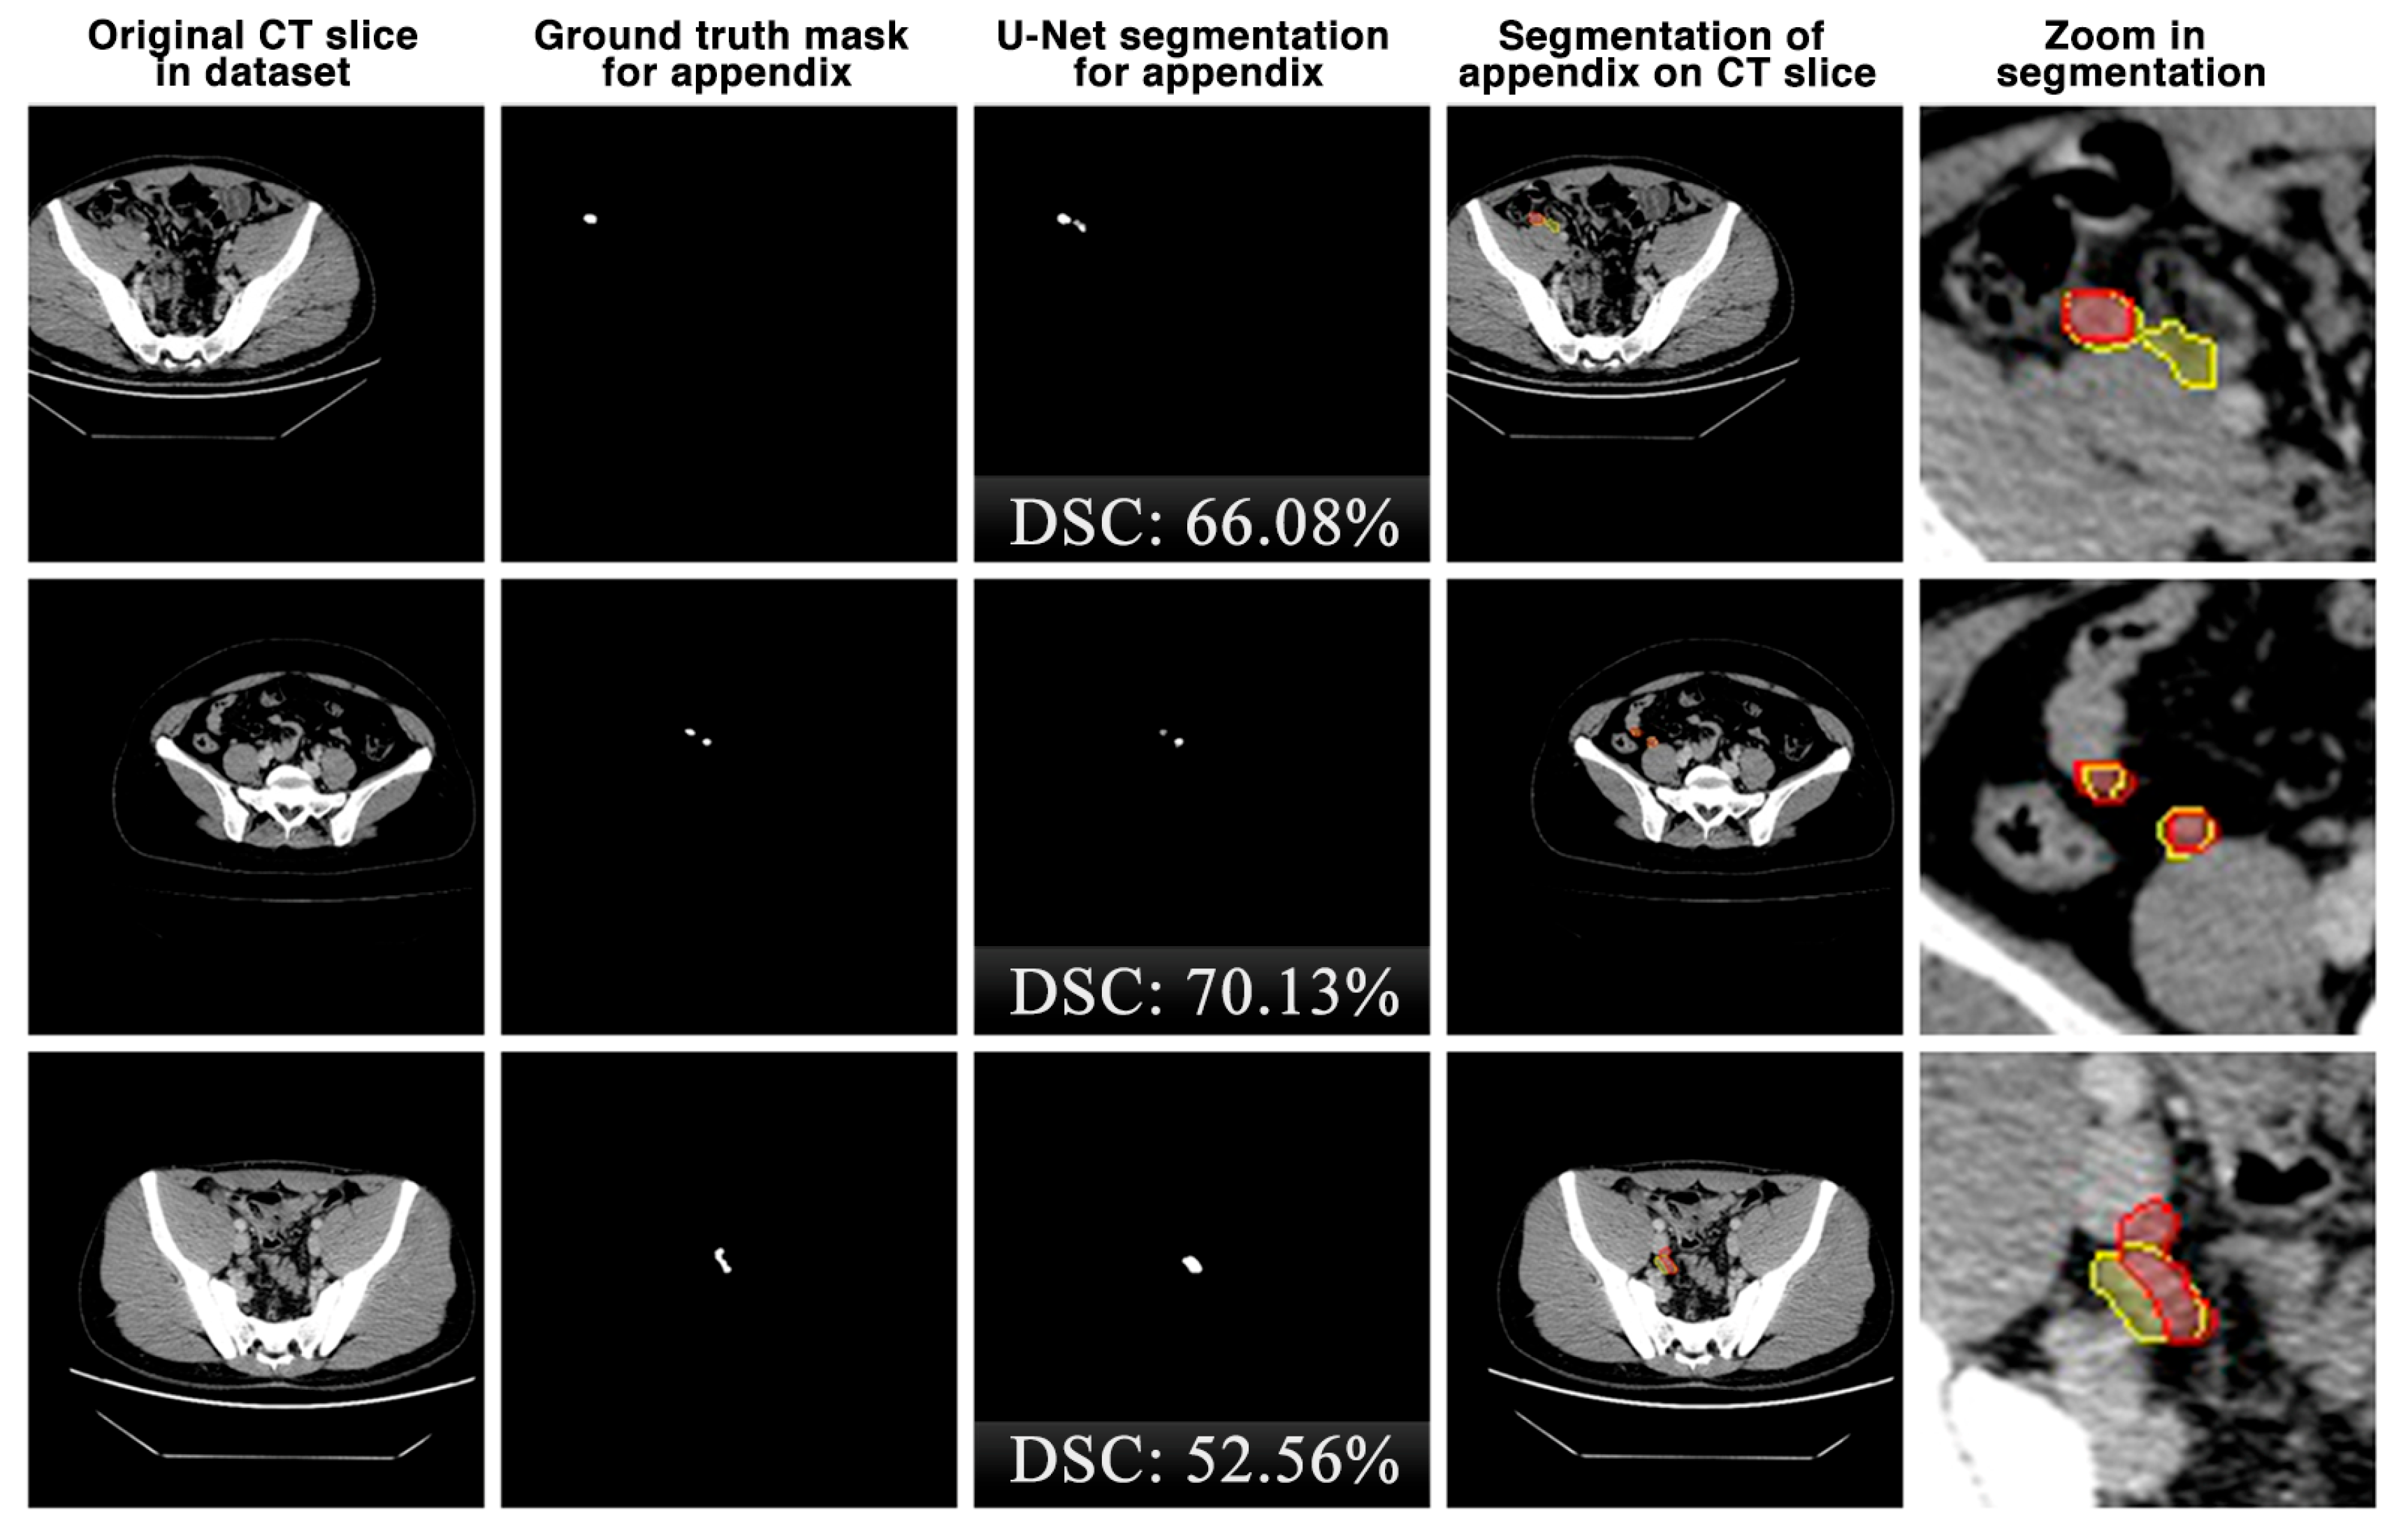

The appendix regions successfully detected and segmented on CT slices using the proposed U-Net deep learning architecture during the experimental studies are shown in Figure 6. While the mask of an original CT slice in Figure 6a containing the appendix region delineated by the expert is shown in Figure 6b, the segmentation of the appendix by the proposed U-Net deep learning architecture is shown in Figure 6c along with the DSC score. On the other hand, the overlap of the expert mask and the U-Net segmentation on the CT slice is also shown in Figure 6d and its zoomed version is shown in Figure 6e. As can be seen, the proposed U-Net-based deep learning architecture is very successful in segmenting the appendix CT scans and is very close to the expert GTs. Some examples of the segments that the proposed model has difficulty in detecting are shown in Figure 7. When analysing Figure 7, it is clear that the model cannot successfully detect some slices. The lack of success in these slices can be attributed to the fact that the appendix region is close to or adjacent to other areas, or the boundaries of the region are similar to those of the neighbouring areas. Such cases stood out as instances where the boundaries of the appendix were blurred and the model was unstable.

Figure 6.

The appendix regions successfully detected and segmented on CT slices using the proposed U-Net deep learning architecture during the experimental studies. Red: ground truth mask for appendix, yellow: U-Net segmentation for appendix.

Figure 7.

Some examples of unsuccessful appendix detection and segmentation by the proposed U-Net model. Red: ground truth mask for appendix, yellow: U-Net segmentation for appendix.